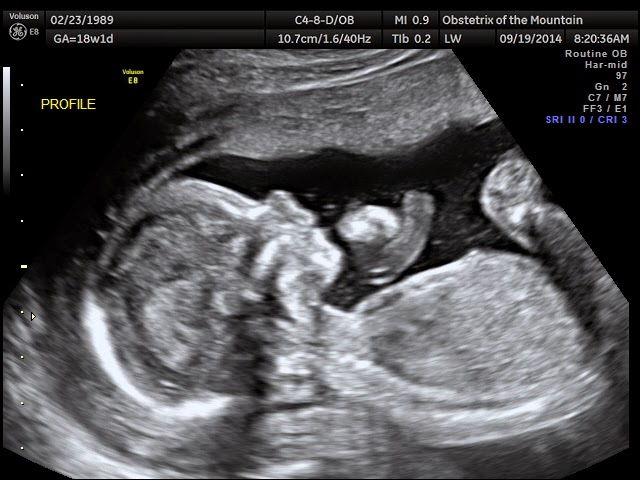

Today we went in for our 18 week ultrasound! Wow! It was incredible. We were able to see our sweet baby's profile, little beating heart, brain, kidneys, spine, irises, stomach, bladder, cute bum, legs, feet, etc. We were in awe during the entire ultrasound. What a miracle!! At one point the ultrasound tech thought the baby had hiccups because it was bouncing around so much. She tool a closer look only to find that our sweet baby was just stretching out it's legs repeatedly and pushing off my uterine wall. It almost looked like it was jumping! What a funny, cute baby. I am measuring 1 day ahead of schedule, which basically means we are right on track since that's a minimal margin of error. We of course also found out the gender, but that's for the next post. :) It was such an incredible, spiritual experience. We could not be more excited for this sweet baby to join our family. Here are a few pictures of our sweet little one.

The baby's profile. I love this picture and I love how the baby is resting it's arm on the umbilical cord.